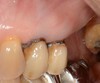

Chez cette patiente de 76 ans, une dent pilier de bridge s’est fracturée et n’est plus conservable.

Le bridge a été fraisé pour conserver les prémolaires. La deuxième molaire fracturée, pilier du bridge, a été extraite. La troisième molaire est conservée.

La simulation logicielle en 3D montre le projet implantaire.